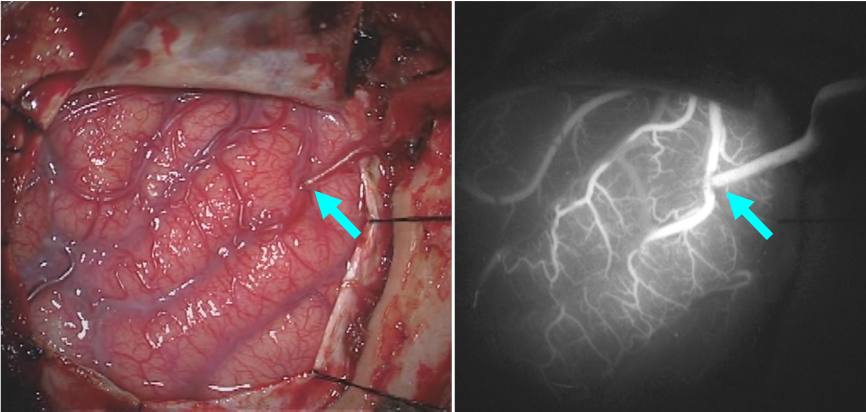

慢性期脳主幹動脈閉塞・もやもや病

脳の動脈が徐々に狭窄、閉塞し脳血流の低下し脳梗塞の発症、再発を起こすことがあります。脳血流の予備能が低下している場合、頭皮の動脈を脳表の動脈と吻合して脳血流を補う手術(直接バイパス術)を行い,脳梗塞の再発を予防します。

もやもや病は比較的まれな病気ですが、両側の内頸動脈が進行性に細くなり、周囲に細かいモヤモヤ血管が増生してきます。小児~若年期は一過性脳虚血発作や脳梗塞,壮年~高齢では脳出血で発症することが多いと言われています。直接バイパス術や、脳表を頭皮や筋肉などの組織で覆って血管新生を促して血流を補う手術(間接バイパス術)を行い脳梗塞や脳出血を予防します。

術前のMRA画像です。矢印の部位で動脈が狭窄、閉塞しています。

もやもや病に対する直接バイパス術の術中写真です。矢印の部位で血管吻合を行っています。